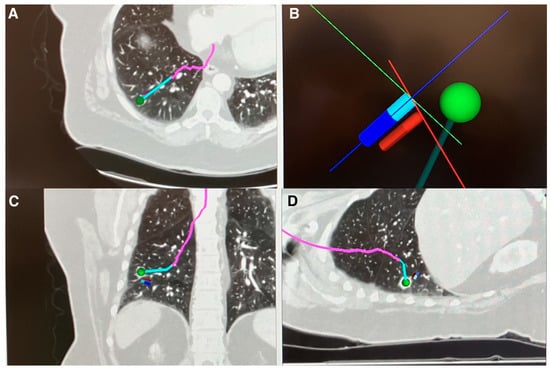

- Kalchiem-Dekel, O.; Fuentes, P.; Bott, M.J.; Beattie, J.A.; Lee, R.P.; Chawla, M.; Husta, B.C. Multiplanar 3D fluoroscopy redefines tool-lesion relationship during robotic-assisted bronchoscopy. Respirology 2021, 26, 120–123. [Google Scholar] [CrossRef]

- Reisenauer, J.; Duke, J.D.; Kern, R.; Fernandez-Bussy, S.; Edell, E. Combining Shape-Sensing Robotic Bronchoscopy with Mobile Three-Dimensional Imaging to Verify Tool-in-Lesion and Overcome Divergence: A Pilot Study. Mayo Clin. Proc. Innov. Qual. Outcomes 2022, 6, 177–185. [Google Scholar] [CrossRef]